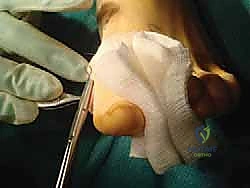

a. Medial Longitudinal Incision:

We begin with a medial longitudinal incision. This incision extends precisely from the palpable first tarsometatarsal (TMT) joint proximally, distally along the medial flare of the first metatarsal, to the medial aspect of the proximal phalanx.

This length is crucial. If we anticipate a concomitant proximal phalangeal osteotomy, such as an Akin, we can extend this incision slightly more distally.

As we deepen the incision through the skin and subcutaneous tissue, be acutely aware of the dorsal medial cutaneous nerve. Use blunt dissection with Metzenbaum scissors to carefully identify and retract this nerve dorsally and protect it throughout the procedure. Any direct trauma or excessive traction can lead to postoperative neuroma or paresthesia.

b. Medial Capsular Incision and Bunionectomy:

Once the nerve is protected, we sharply incise the medial capsule in a single, longitudinal direction. This provides excellent exposure of the medial eminence of the first metatarsal head.

Now, using an oscillating saw, we will resect the medial eminence. The key here is precision: resect it 1 mm medial to the sagittal sulcus.

This ensures we remove the prominent bone without over-resecting, which could lead to a postoperative varus deformity of the hallux. Use a small rongeur or rasp to smooth any sharp edges after resection.